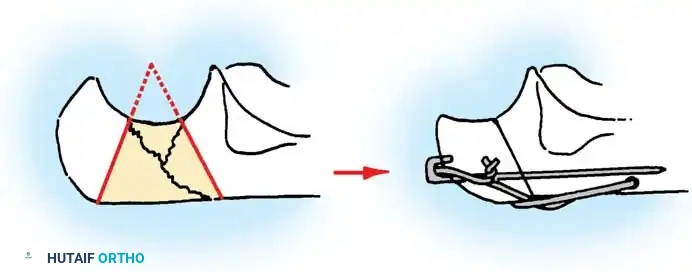

- Bone Preparation: Smooth the remaining proximal end of the ulna. If the midportion of the olecranon is comminuted but the proximal tip is intact, the central comminuted segment can be excised (Barford technique). The osteotomies must be directed accurately along the radius of the trochlear curve to reconstitute a smoothly curved notch.

Fig. 54-57 Technique of excision of central one third of olecranon process (Barford, 1972). It is critical to err by making the radius of the notch too large, rather than too small.